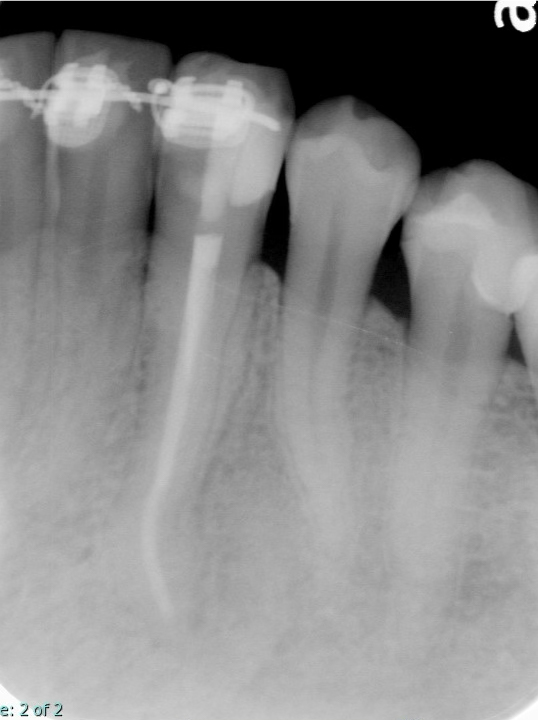

湾曲した根管でも、歯をできるだけ削らずに初回治療を行えたケース(低侵襲な根管治療)

根管治療の症例

術前

術後2年4ヶ月

根管が大きく曲がっている歯は、器具操作が難しく、治療のために削る量が増えやすい傾向があります。本症例では、根管形態を正確に把握したうえで、湾曲根管に適した器具選択と精密な操作を行い、必要最小限の切削で根管治療(初回治療)を完了しました。

年齢性別 30代・女性

主訴 下の歯ぐきが腫れている

治療部位 左下3番

治療内容 初回根管治療(湾曲根管に対し、削る量を抑えた形成・根管充填の方針)

治療回数 2回

リスク副作用 治療後に痛みや違和感が出ることがあります。根管の形態によっては治療回数が増えたり、再治療が必要になる場合があります。

難しい形態ほど、治療結果は「勘」ではなく「手順と精度」に左右されます。歯内療法の専門医が担当することで、湾曲根管のような難易度の高いケースでも、歯質をできるだけ温存しながら、再発リスクを下げる治療を目指せます。